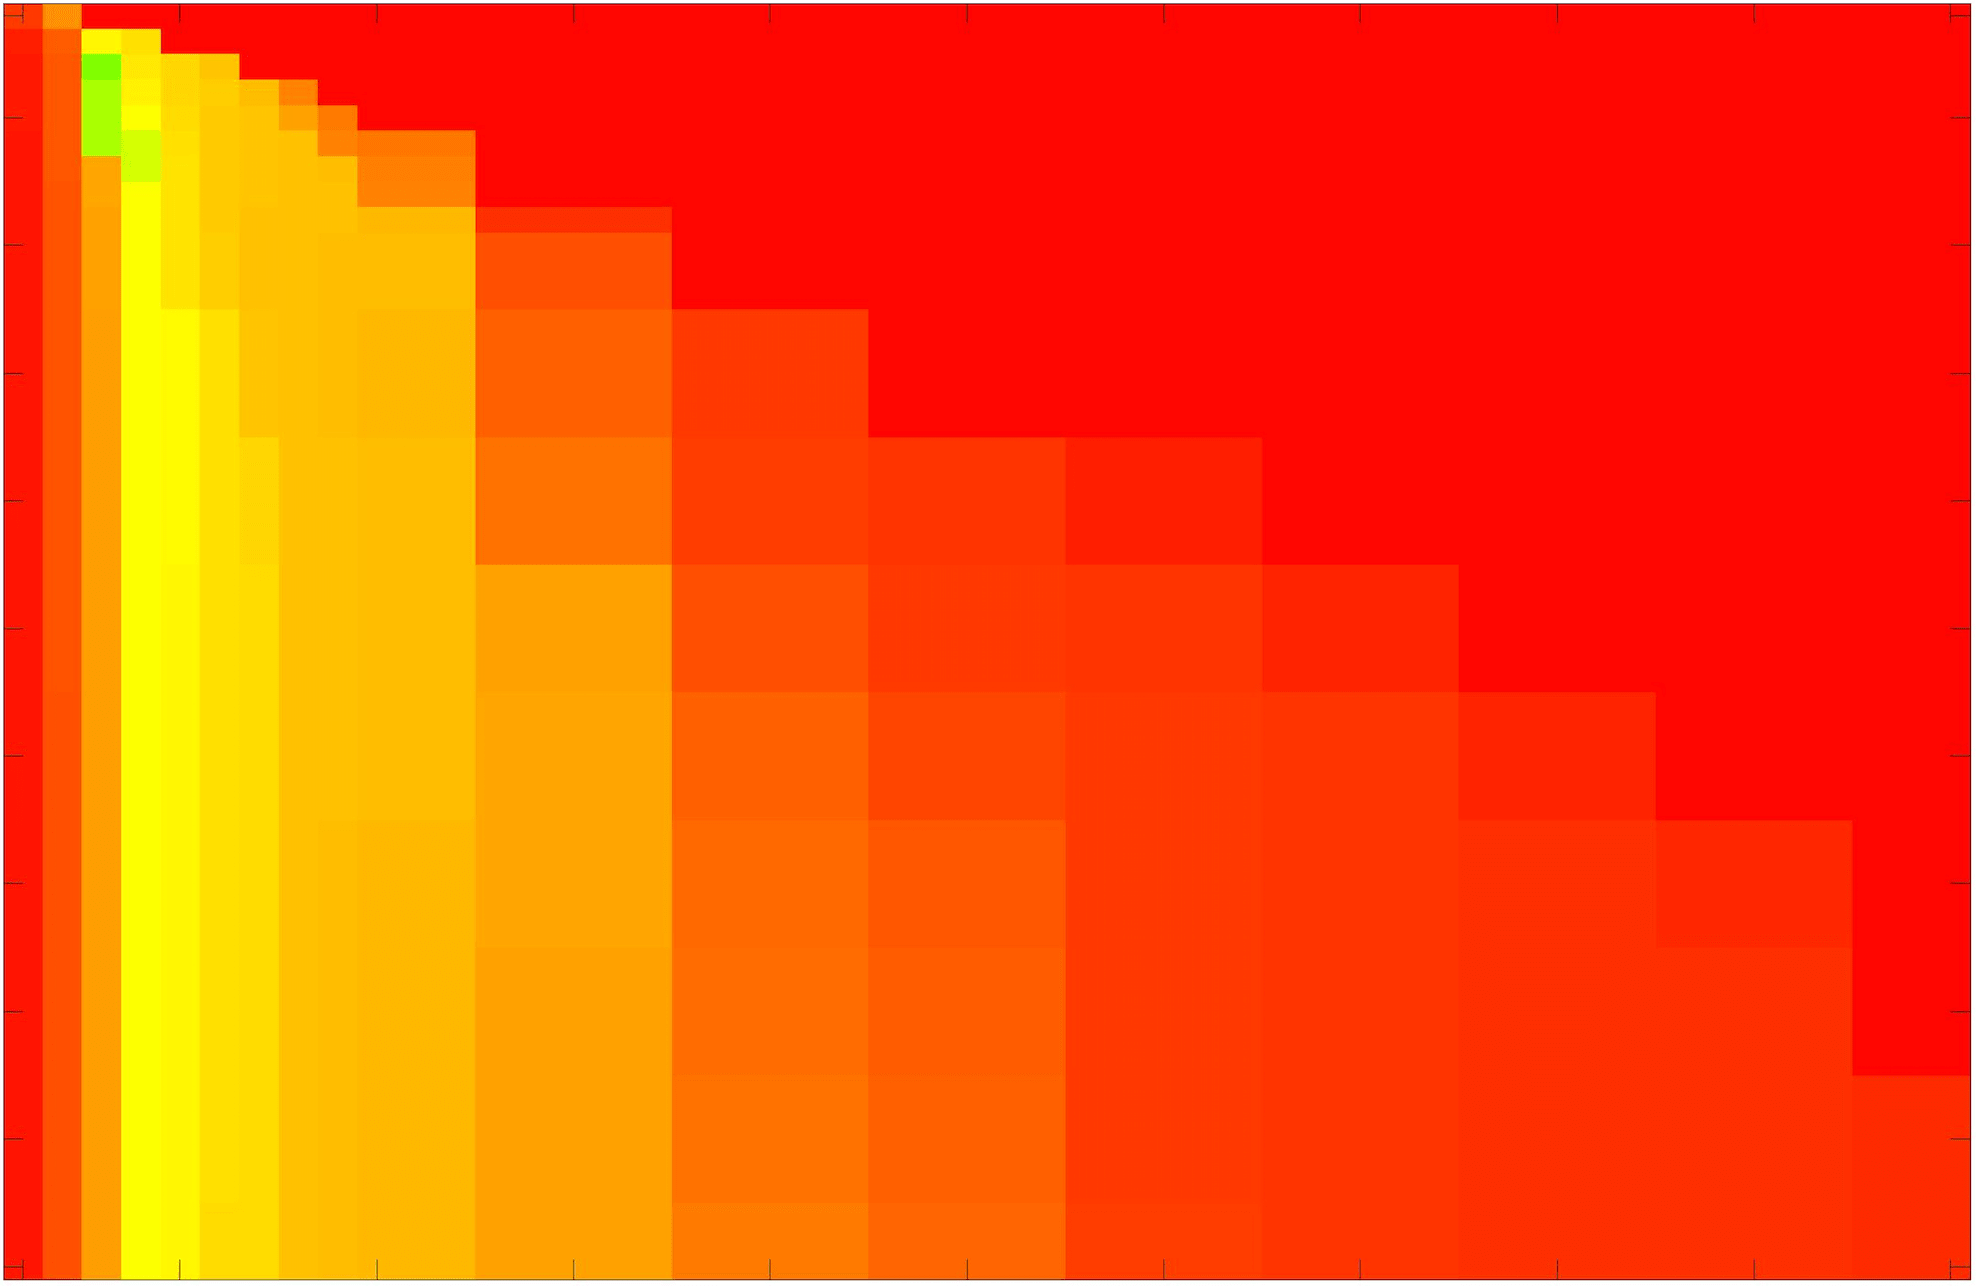

where refers to the number of points in the enclosed region. This takes values in the range , with higher TC values indicating a more accurate segmentation. In the following we will represent accuracy visually from red () to green (), with the intermediate scaling of colours used shown in Fig. 8. This will be particularly relevant in §7.2.

The TC values for the parameter sets are presented as heatmaps in Figs. 11–13. A heatmap is a convenient way to display accuracy results for hundreds of tests concisely. In Fig. 9 we give an example heatmap with the same axes used for those in Figs. 11–13. For each of the combinations of parameter values we give the TC value of the segmentation result and represent it by the appropriate colour. The corresponding colour scale is shown in Fig. 8. Qualitatively, the more green areas of the heatmap the more accurate the model is for a wider set of parameters. Example results for Test Image 5 when varying (with ) for the proposed model are given in Fig. 10. Here it can be seen what each accuracy result corresponds to visually.

Note. The axes have been removed from the heatmaps in Figs. 11–13 for presentational clarity. However, to be explicit, the axes used in all heatmaps are the same as those in Fig. 9.